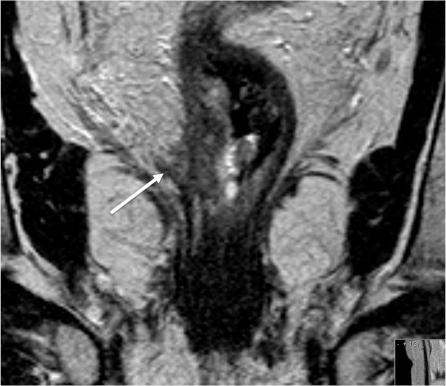

基于表格的直肠癌报告。

Proforma-based reporting in rectal cancer.

The improvements in outcomes associate with the use of preoperative therapy rather than postoperative treatment means that clinical teams are increasingly reliant on imaging to identify high-risk features of disease to determine treatment plans. For many solid tumours, including rectal cancer, validated techniques have emerged in identifying prognostic factors pre-operatively. In the MERCURY study, a standardised scanning technique and the use of reporting proformas enabled consistently accurate assessment and documentation of the prognostic factors. This is now an essential tool to enable our clinical colleagues to make treatment decisions. In this review, we describe the proforma-based reporting tool that enables a systematic approach to the interpretation of the magnetic resonance images, thereby enabling all the clinically relevant features to be adequately assessed.

摘要

术前治疗而非术后治疗带来的结果改善意味着临床团队越来越依赖于影像学来识别疾病的高危特征以确定治疗方案。对于许多实体瘤,包括直肠癌,已经出现了用于术前识别预后因素的验证技术。在 MERCURY 研究中,标准化的扫描技术和报告表格的使用使得对预后因素的准确评估和记录成为可能。这现在是我们的临床同事做出治疗决策的重要工具。在这篇综述中,我们描述了基于报告表格的报告工具,它使我们能够对磁共振图像进行系统的解读,从而能够充分评估所有与临床相关的特征。